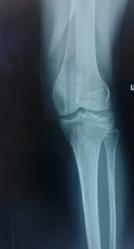

Management de tratament în fracturile de platou tibial

Treatment management in tibial plateau fractures

Summary: Tibial plateau fractures are complex injuries, which can have different degrees of severity. Their incidence is increasing in recent years, and the resulting potential complications are a challenge for the orthopedist. They can be both simple, without displacement, and complex, with significant local tissue damage, integument, meniscus, ligaments and neuro-vascular damage, which can compromise the viability of the pelvic limb. Because of this, it requires a complex therapeutic management.Epidemiologie

Diagnostic imagistic

Articulația genunchiului trebuie sistematic examinată în vederea decelării

Schatzker III, Osteosinteză cu șuruburi percutană

Schatzker VI, Reducere sângerândă și osteosinteză cu 2 plăci

fracturilor cu separare sau înfundare a platourilor tibiale, precum și a leziunilor de părți moi asociate ligamentare sau de menisc.

Se practică radiografii standard, examinare CT sau RMN.

Radiografiile se fac în cel puțin 3 incidențe: antero-posterioară, laterală și notch intercondilar.

Incidența antero-posterioară poate decela: o bandă osteoscerotică intensificată, specifică fracturii cu înfundare, separarea unui fragment osos, incongruență articulară femuro-tibială. O înfundare mai mare de 6 mm sau/și o incongruență articulară cu lărgirea acesteia mai mult de 5 mm sunt sugestive pentru leziuni de menisc lateral, ligament colateral lateral sau ligament încrucișat posterior(5). O înfundare sau lărgire articulară mai mare de 8 mm este deseori asociată cu o leziune de menisc medial(6).

În baza examenului radiologic au fost propuse mai multe clasificări, dar cea mai folosită este cea a lui Schatzker:

Schatzker I: fracturi cu separare hemiplatou extern

Schatzker II: fracturi cu separare și înfundare hemiplatou extern

Schatzker III: fracturi cu înfundare hemiplatou extern

Schatzker IV: fracturi hemiplatou intern

Schatzker V: fracturi hemiplatou extern și intern

Schatzker VI: fracturi cu extensie metafizo-diafizară